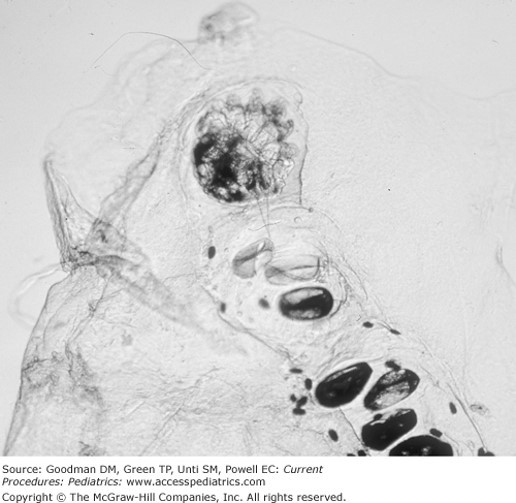

The correct answer is “D.” Pruritic rashes that concentrate in web spaces and display linear burrows are classic for scabies. (See Figure 33–32.) A mineral oil preparation (scabies prep) is used to confirm the diagnosis. (See Table 33–7.) Scabies mites infest the stratum corneum, so they are readily detected by skin scraping, application of a drop of mineral oil, and observation of mites, eggs, or scybala (feces) under the microscope. Biopsy is usually unnecessary to diagnose scabies. Not everyone has immediate access to a microscope, so it is reasonable to treat empirically for scabies.